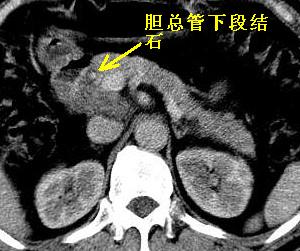

首先,胆总管下端结石梗阻伴肝内胆管扩张可确定。

胆总管下端结石。

男性,54岁,皮肤黄染,搔痒一周余.b超示肝左叶回声异常.初步诊断1胆总管下段结石2胆囊结石伴慢性胆囊炎请各位战友帮忙看一下肝脏多发低密度如何解释恰当.增强效果不是很好.请大家见谅.